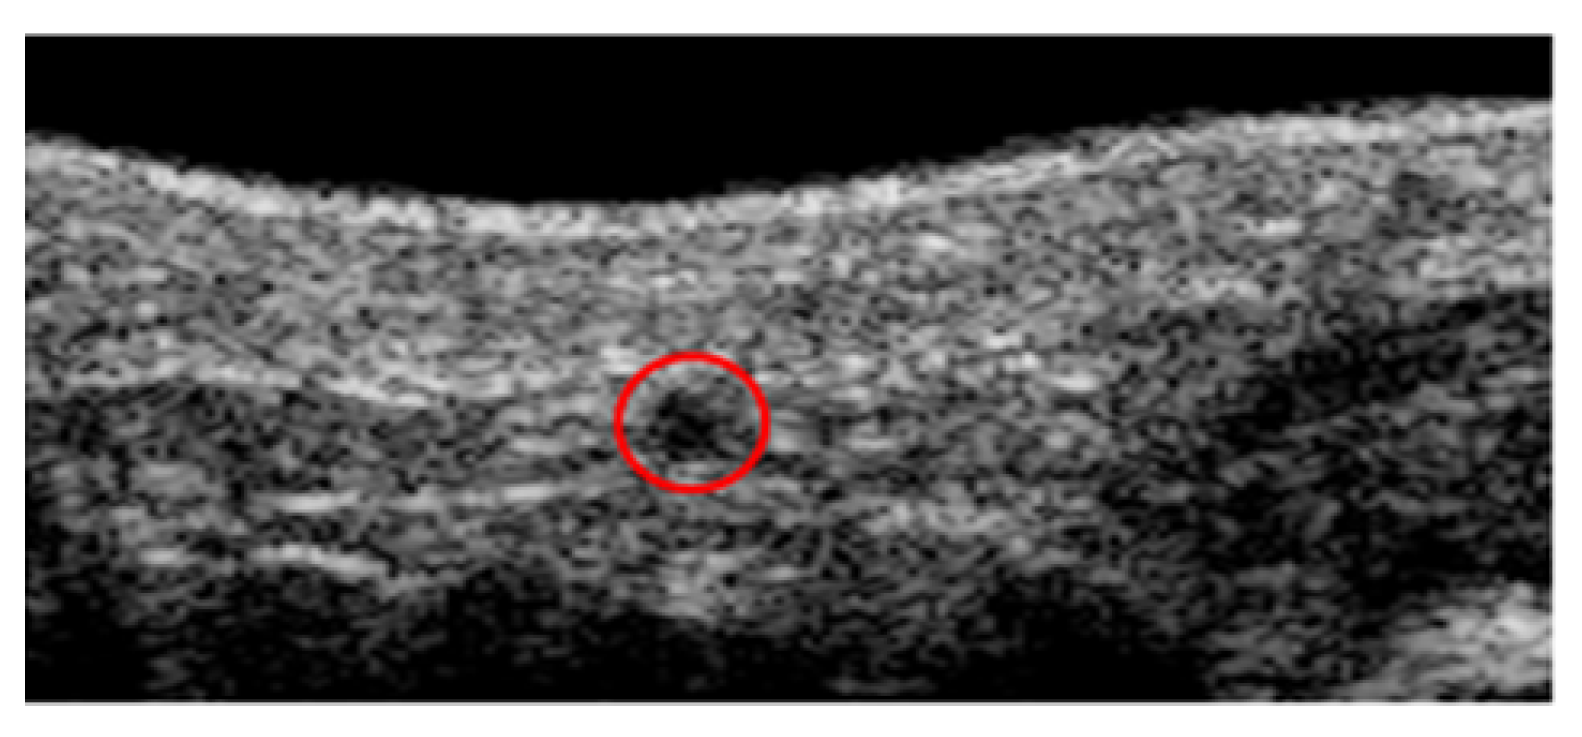

- Yu, Y.; Acton, S. Speckle reducing anisotropic diffusion. IEEE Trans. Image Process. 2002, 11, 1260–1270. [Google Scholar]

- Narayan, N.S.; Marziliano, P.; Kanagalingam, J.; Hobbs, C.G. Speckle in ultrasound images: Friend or FOE? In Proceedings of the 2014 IEEE International Conference on Image Processing (ICIP), Paris, France, 27–30 October 2014. [Google Scholar]